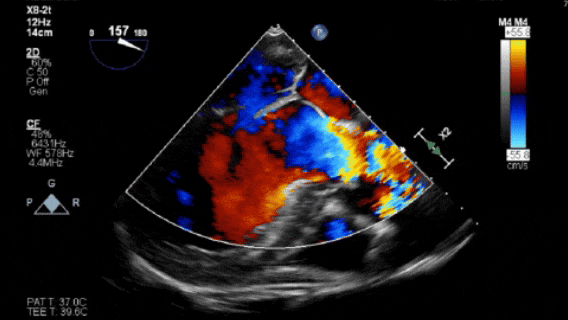

术前食道超声

经超声提示:主动脉窦部瘤样增宽并主动脉瓣关闭不全伴钙化;升主动脉瘤样增宽;左房、左室大;二尖瓣钙化,为老年性退行性病变;主动脉硬化;左室收缩功能减低;彩色血流示:主动脉瓣上血流速度加快,瓣下反流(大量);二尖瓣反流(少-中量)。EDV:343ml ESV:184ml EF:46% FS:23% SV:159ml。经详细评估患者CTA检查后,瓣环偏大,暂无适合介入瓣膜,患者可考虑外科手术,家属及患者一致决定择期介入手术。2月前因上述症状加重,再次当地医院住院对症治疗,症状好转后就诊西京医院。